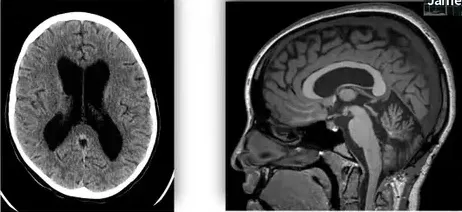

没想到,那边的医生给了我们一束光,将我们从绝境中拉了出来。我们是奔着James T.Rutka教授去的,他是多伦多大学儿童病院、亚瑟和索尼亚拉巴特脑瘤研究中心主任,对欢欢这样的的儿童脑干胶质瘤经验丰富,而且即使需要辅助治疗,他也能一并制定治疗计划,我更放心。

案例来源:Rutka教授演讲分享手术案例